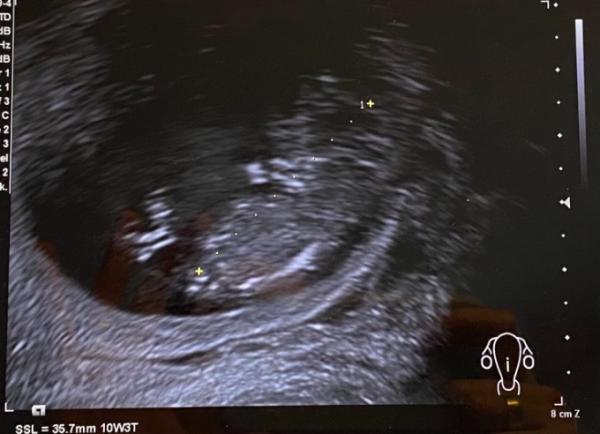

Hallo Mädels, komme auch gerade vom FA! Das Baby hat ganz wild gezappelt und Herzchen hat schön regelmäßig geschlagen! Das war so ein schönes Gefühl! Nachher hat der FA mir anhand der Bilder gezeigt das ich eine Vorderwandplazenta (ich glaube das meinte er) habe! Ich soll jetzt liegen , nichts heben und kein Sex, sonst kann das innerlich anfangen zu bluten?! Es ist jetzt für das Baby nicht schlimm meinte er aber ich bin jetzt ganz durcheinander weiß jemand was er genau meinte? Was das ist? Und kann mich beruhigen? Anbei ein Bild vom Zappelflo, vielleicht erkennt jemand schon das Geschlecht? Oder hat eine Theorie dazu ?

Bild zu Zurück vom FA - verunsichert - Forum für Juli - Mamis